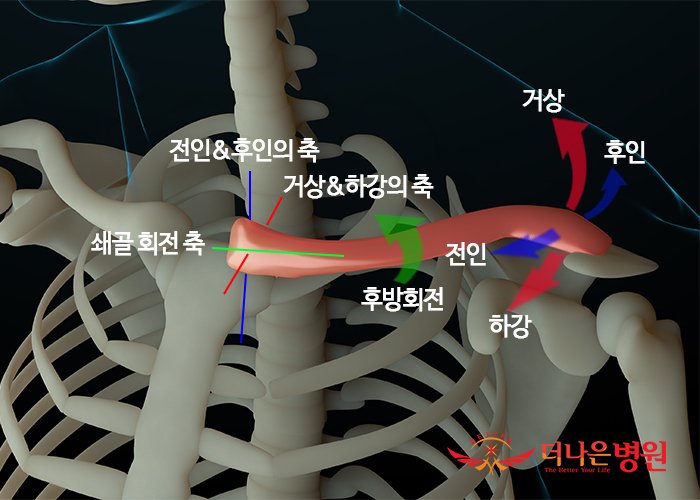

쇄골의 골운동형상학은 3도의 자유도를 가지고, 거상과 하강, 전인과 후인, 그리고 쇄골 뼈의 장축에 대한 회전을 할 수 있습니다. 어깨관절의 모든 기능적 움직임에는 다른 3가지 관절들과 마찬가지로 흉쇄관절에서 쇄골의 움직임이 포함되어 움직임의 안정성과 움직임의 양을 조절하게 됩니다.

거상(Elevation)과 하강(Depression)

흉골의 관절면에서 쇄골의 거상과 하강은 어깨를 으쓱거리는 동작을 할 때 일어나는 움직임으로 전후축에 대해 전두면에 거의 평행하게 일어나게 됩니다. 움직임의 양은 거상시에 45도의 최대 거상과 하강시에 10도의 최대 하강이 일어나게 됩니다. 쇄골의 거상과 하강은 견쇄관절, 견흉관절의 움직과 결합하여 나타나게 되며, 견갑골의 운동과 관계가 있습니다. 쇄골의 거상과 하강에 대한 관절운동형상학은 흉쇄관절의 세로 관절면을 따라 일어나게 됩니다.

쇄골의 거상은 쇄골두의 볼록면이 흉골의 오목면에 대해 상방으로 구르고 이와 동시에 하방으로 미끄러짐을 할 때 일어나게 됩니다. 이때 늑쇄인대는 쇄골의 위치를 고정시키고 움직임을 제한하는데 중요한 역할을 하게 됩니다. 쇄골의 하강은 쇄골두가 하방으로 구르고, 상방으로 미끄러짐을 할 때 일어나게 되며, 완전히 하강된 쇄골은 쇄골간인대와 관절낭인대의 위쪽 부분에 의해 움직임을 제한 받게 됩니다.

전인(Protraction)과 후인(Retraction)

흉쇄관절에서 흉골의 관절면에서 쇄골의 전인과 후인은 어깨복합체를 앞, 뒤로 움직이는 동작을 할 때 일어나는 움직임으로 수직축에 대해 수평면에 거의 평행하게 일어나게 됩니다. 회전축은 특정 움직임을 위해 관절의 볼록면을 가로지르기 때문에, 쇄골의 전인과 후인을 위한 회전의 수직축은 흉골을 가로지르고 있습니다. 전인과 후인에 대한 운동범위는 앞쪽과 뒤쪽 방향으로 각가 거의 15도~30도의 움직임이 일어나게 됩니다. 수평면에 대한 쇄골의 전인과 후인 움직임은 거상 및 하강 움직임처럼 견쇄관절, 견흉관절의 움직임과 결합하여 나타나게 되며, 견갑골의 운동과 관계가 있습니다. 쇄골의 전인과 후인에 대한 관절운동형상학은 흉쇄관절의 가로면을 따라서 일어나게 됩니다.

흉쇄관절에서 후인은 쇄골의 오목한 관절면이 흉골의 볼록면에 대해 후방으로 구르고 미끄러짐을 할 때 일어나게 됩니다. 후인의 끝범위에서 늑쇄인대의 앞쪽 다발과 앞쪽 관절낭인대의 신장으로 인해 움직임을 제한 받게 되고, 흉쇄관절에 대한 전인의 관절운동형상학운 운동이 앞쪽에서 일어난다는 것을 제외하면, 후인의 관절운동형상학과 같습니다. 최대의 전인은 전방으로 최대한 손뻗기와 같은 운동을 하는 동안 일어나게 됩니다. 늑쇄인대의 뒤쪽 다발, 뒤쪽 관절낭인대, 그리고 견갑골 후인근육의 단축은 쇄골의 전인을 제한하게 됩니다.

쇄골의 축회전

흉쇄관절의 세번째 자유도는 쇄골의 장축에 대한 쇄골의 회전입니다. 쇄골의 회전은 주로 견쇄인대 및 오훼쇄골인대 등의 쇄골에 부착된 인대의 신장에 의해 발생되게 됩니다. 팔을 들어올릴 때 쇄골은 후방으로 거의 40도~50도 회전이 일어나게 되고, 다시 원위치로 돌아올 때 후방으로 회전되어 있는 쇄골은 전방으로 회전되어 원위치로 돌아오게 됩니다. 쇄골의 회전에 대한 관절운동형상학에는 관절원판의 외측면에 대한 쇄골두의 축돌림이 있습니다. 쇄골의 완전한 후방회전, 즉 어깨를 최대 굴곡시키는 동작은 흉쇄관절의 관절면이 가장 가까워지는 잠긴 위치가 됩니다.